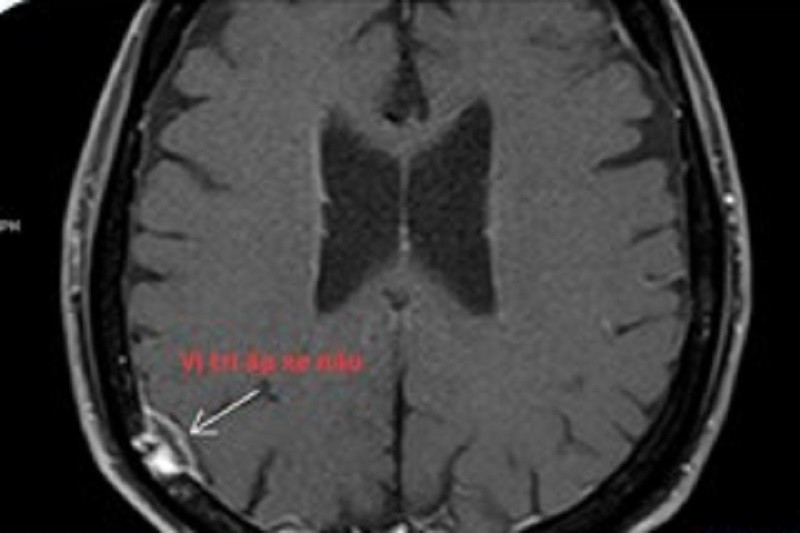

Bệnh nhân đã bị vi khuẩn tấn công gây áp xe não, đe dọa tính mạng (vùng áp xe tại vị trí mũi tên)

Kết quả kiểm tra hình ảnh phát hiện một ổ áp xe trong não người bệnh có kích thước khoảng 7x15mm, kèm tổn thương viêm khu trú màng não tại vùng ranh giới giữa thùy chẩm và thùy thái dương bên phải. Điều này cho thấy nhiễm trùng đã lan tới hệ thần kinh trung ương, làm ca bệnh trở nên đặc biệt phức tạp và tiềm ẩn nhiều nguy cơ đe dọa tính mạng.